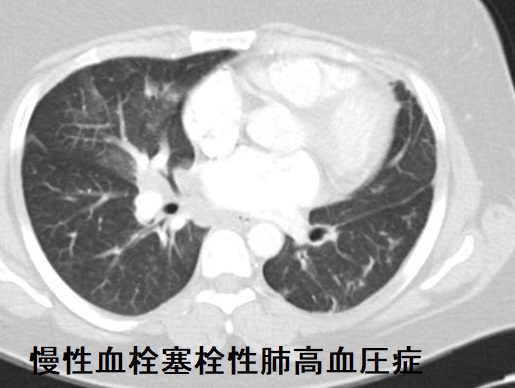

肺高血圧症(慢性血栓塞栓性肺高血圧症)のCT所見は、

- 肺動脈拡大・右心系の拡張

- 斑状のすりガラス影(モザイクパターン)、高吸収域では末梢血管影が目立つ